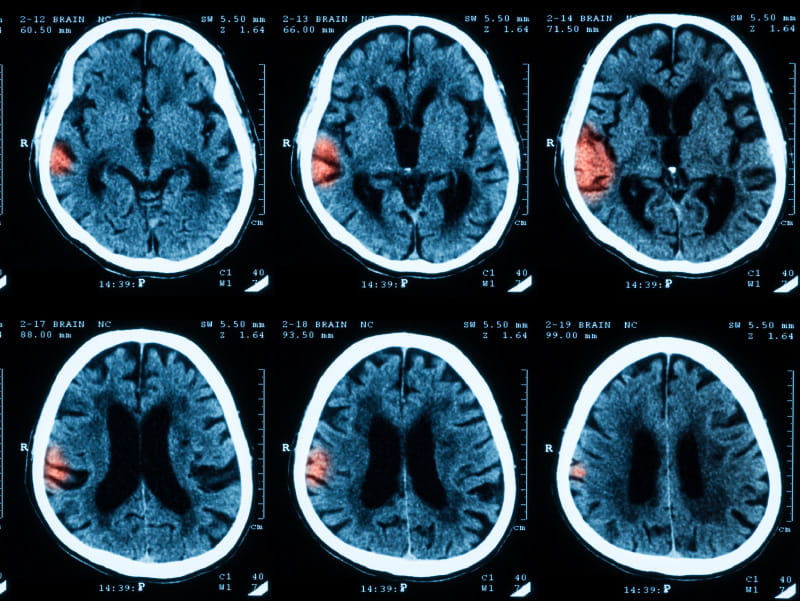

After a median 13 years, strokes had occurred in 410 black women and 3,934 white women. Overall, black women had a 47 percent higher risk for stroke than white women, regardless of age. The risk was highest among black women in their 50s, who had a 3.5-fold increased risk compared to white women of the same age.

Yet, the racial gap in stroke risk across all age groups seemed to disappear when researchers accounted for stroke risk factors, including high blood pressure, weight, smoking, exercise and use of hypertension and cholesterol medications. For black women in their 50s, stroke risk fell considerably but remained higher compared to their white counterparts.